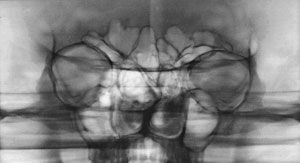

Вид спереди.

1-крыша (свод) черепа;

2-лобная кость;

3-лобная пазуха;

4-ячейки решетчатой кости;

5-костная перегородка полости носа;

6-передняя носовая ость;

7-межверхнечелюстной шов;

8-нижняя челюсть;

9-подбородочный выступ;

10-полость носа;

11-верхнечелюстная пазуха;

12-сосцевидный отросток;

13-глазница.